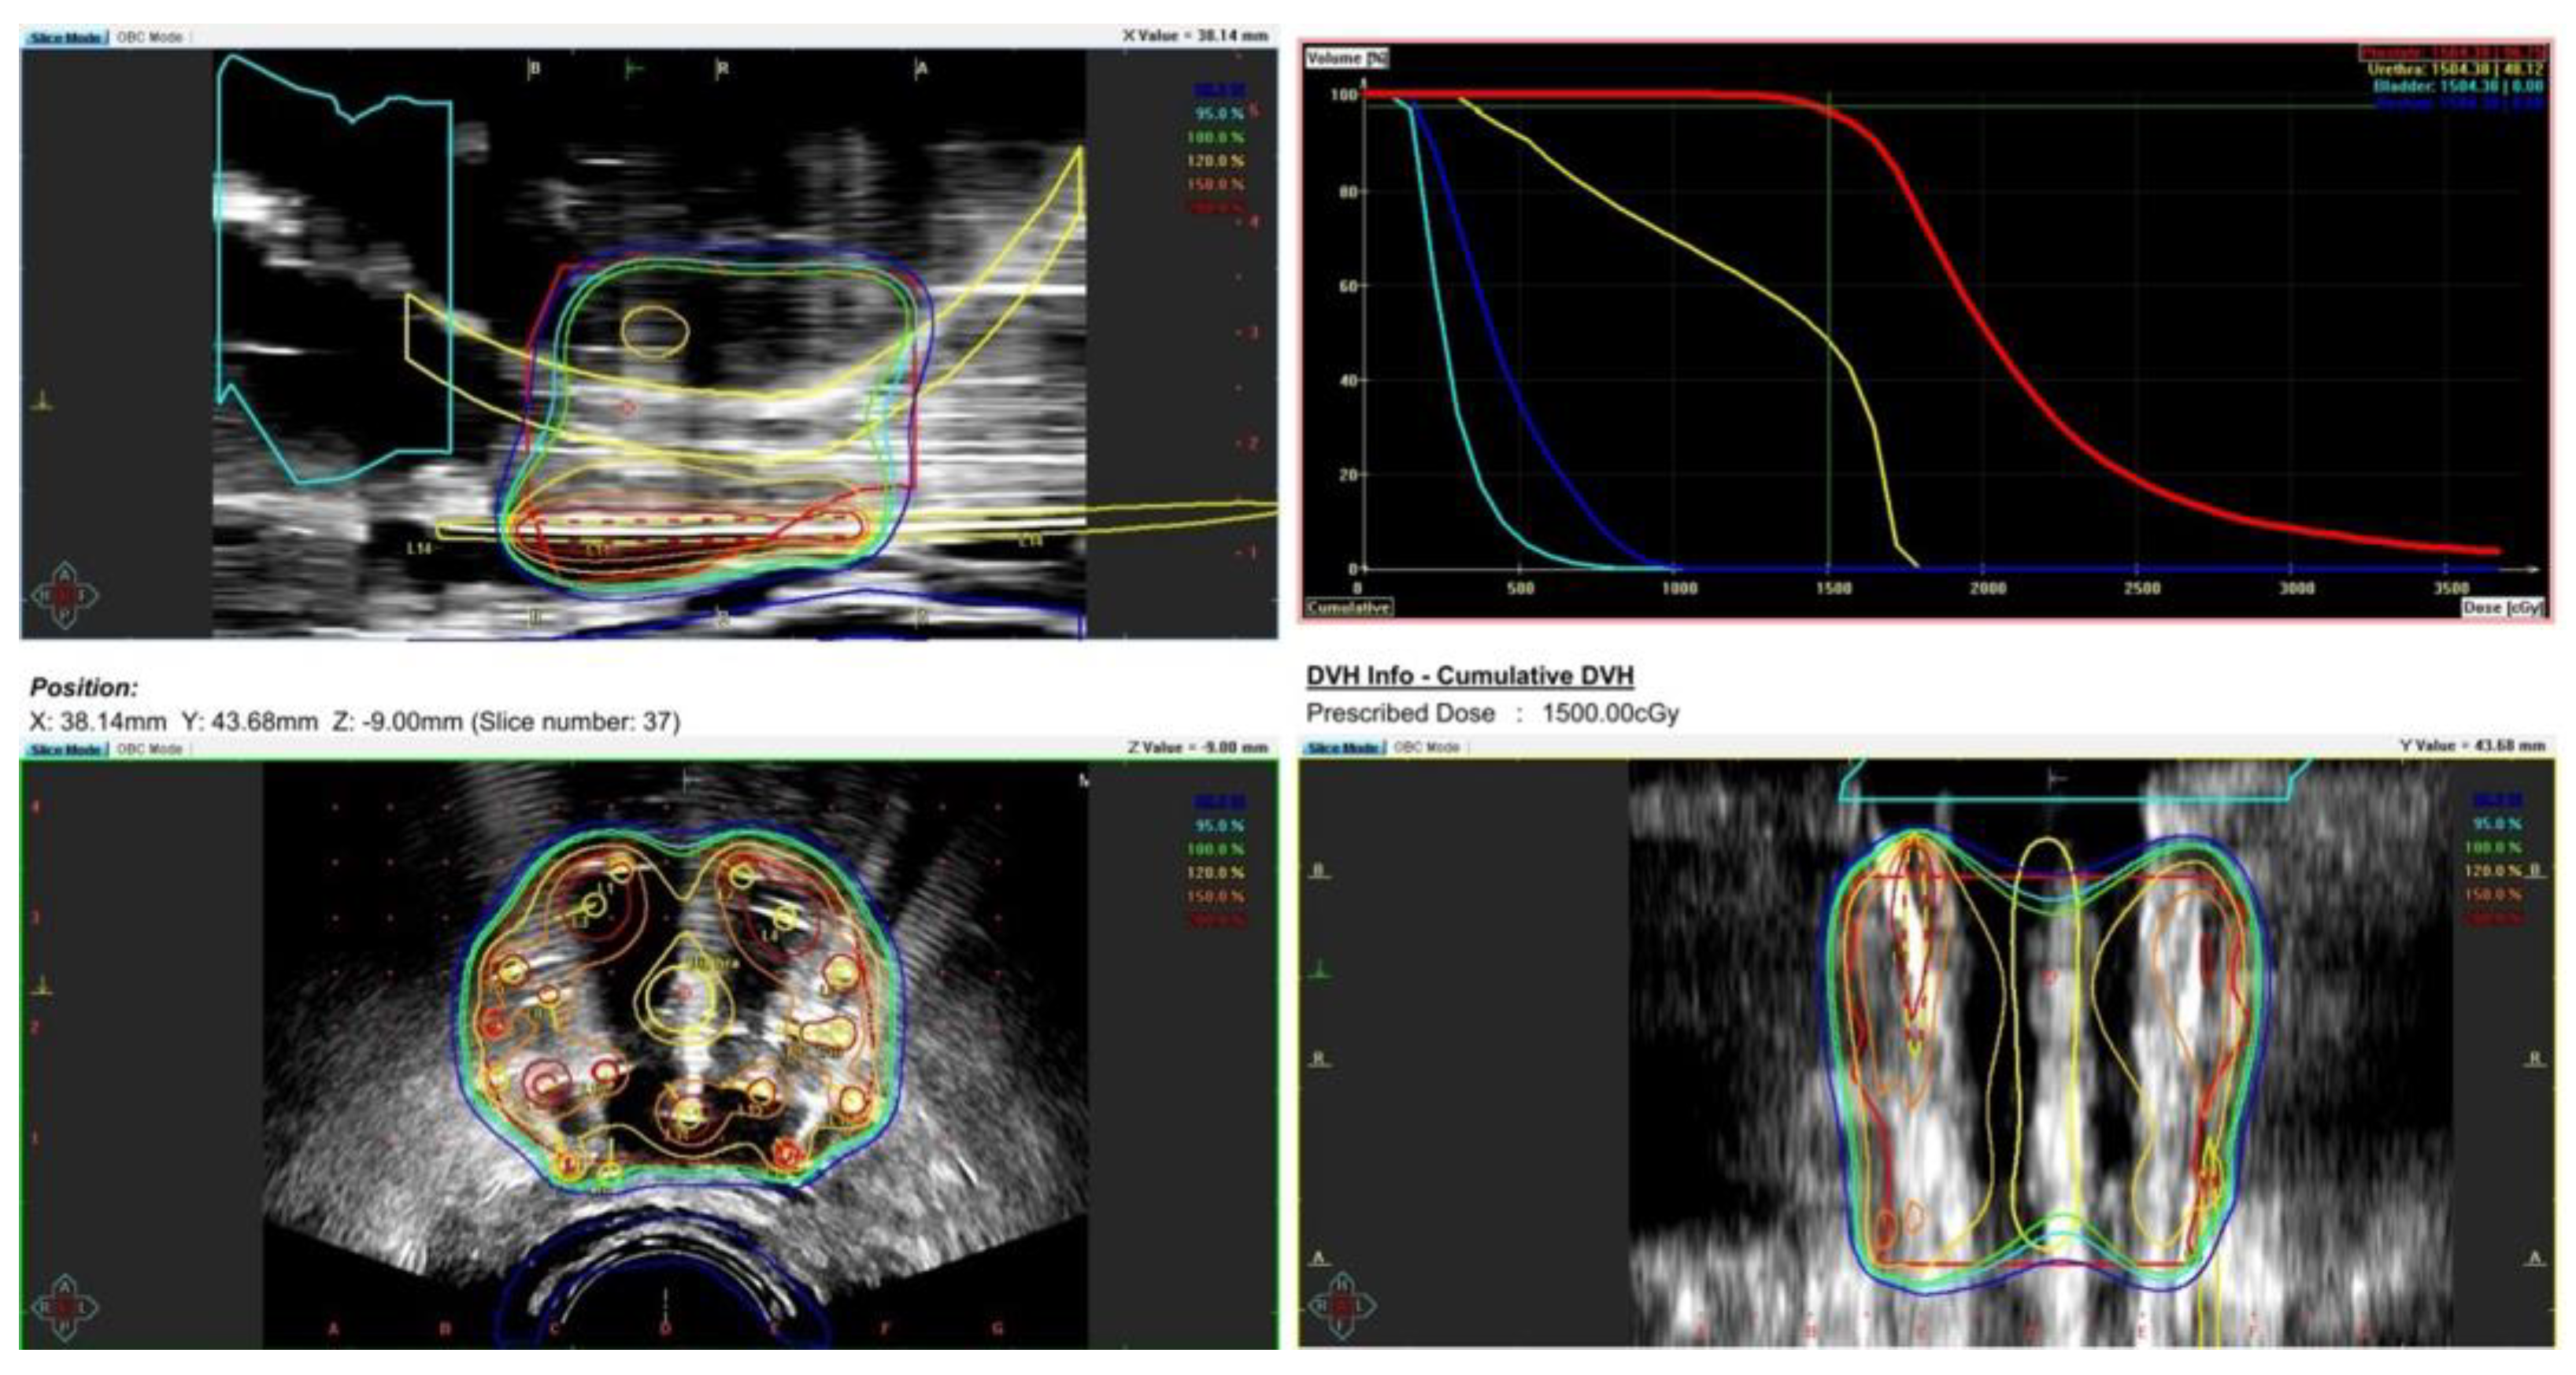

During the planning phase of the radiotherapy treatment course, a PET/CT scan was performed to delineate the metastatic sites accurately and guide radiotherapy planning. The radiotherapy regimen included teleradiotherapy targeting the prostate and affected lymph nodes with radical intent, utilizing a simultaneous integrated boost (SIB) approach with 45 Gy/60 Gy delivered in 25 fractions (Figure 2). Additionally, a high-dose–rate (HDR) brachytherapy boost of 15 Gy was administered in a single fraction to the prostate to achieve maximum local control (Figure 3).

Figure 2. Radiotherapy treatment planning—SIB 45 Gy/60 Gy/25 fx. The treatment plan is visualized across axial, coronal, and sagittal planes, with a corresponding dose–volume histogram illustrating the spatial distribution of radiation doses and treatment field coverage. The color spectrum represents different dose levels, with red indicating the highest dose areas and blue indicating the lowest dose areas. The plan was designed to maximize tumor coverage while sparing healthy tissue.